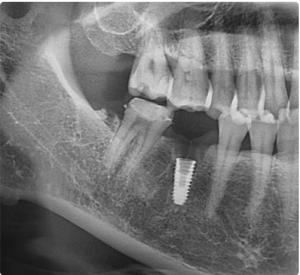

인덕원 임플란트치과, 뼈이식 후 얼마나 오래 유지될까? 안녕하세요.인덕원에서 임플란트 진료를 하고 있는 믿음치과 원장 손동근입니다.   최근 약 5년 전 치료를 받으셨던 환자분이 다시 내원하셨습니다. 당시에는 잇몸뼈가 부족해 고난이도의 뼈이식을...